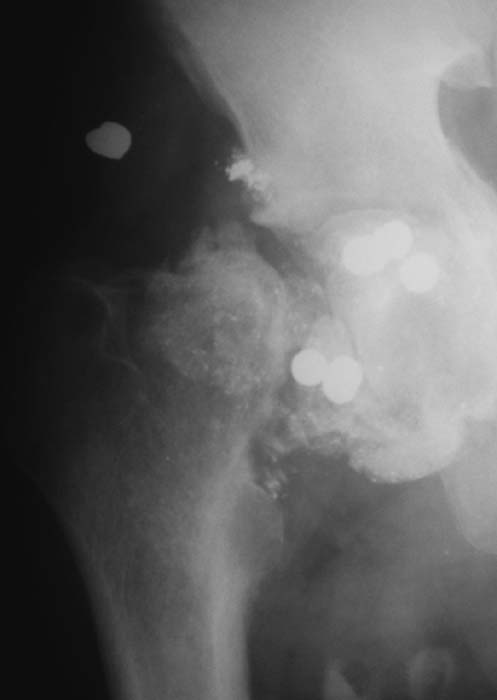

Огнестрельное ранение правого тазобедренного сустава |

Мужчина, 26 лет.Травма в мае 2003 года.Диагноз: огнестрельное ранение правого тазобедренного сустава, открытый перелом головки и шейки правой бедренной кости, проникающее огнестерельное ранение живота. При поступлении в больницу произведена лапаротомия, ПХО раны правой паховой области. Рана в правой паховой области после ПХО заживала первичным натяжением. Проводилась иммобилизация правого тазобедренного сустава гонитной повязкой до 3 месяцев. Спустя 5 месяцев проведена проведена <провокация> - физиопроцедуры на область тазобедренного сустава. Обострения инфекционного процесса нет. Предполагается тотальное эндопротезирование тазобедренного сустава с использованием костного цемента. Вопросы: оценить избранную тактику лечения? Другие варианты лечения?Особенности оперативного вмешательства и послеоперационного лечения?С уважением,А.В.Владзимирский